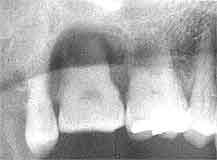

【症例1】 74歳・男性

喪失歯もなく経過良好

【症例2】 55歳・男性

【症例1】

メインテナンス中の患者さんで、歯周疾患進行は弱いが以前から6|の知覚過敏を訴え ていたが、夜も眠れない程の痛みがあったとのこと。カリエス(-) 最大盲嚢 5mm。

【症例2】

最近初診の患者さんで、歯周疾患進行傾向は並程度であるが、上顎臼歯部の骨吸収が著しく 知覚過敏を訴えている。カリエス(-) 口蓋側の盲嚢は根尖に至る。

【症例1】 は完全な歯髄炎末期症状であったので抜髄、CR充填にて経過良好。

【症例2】 は象牙質知覚過敏状態であったが、直近での歯髄炎は避けられない状況と判断して |6ともども抜髄の上連結固定を予定。

何れの症例もカリエスは全く認められず、歯髄の炎症は象牙質知覚過敏によるものと思われる。 このまま歯髄壊死を放置した場合には、何れも根尖病巣に発展して半年後にはいわゆるエンド・ ペリオとして歯槽骨の全てを失って抜歯になるものと思われる。  そしてその時には、根尖部から歯髄壊死に導く上行性歯髄炎として解釈されるものと思われる。